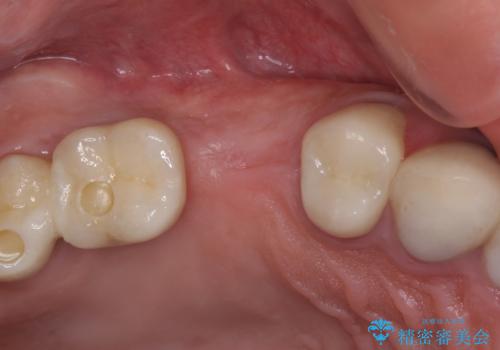

折れてしまった歯 インプラントによる補綴治療

- 咬合力により歯が割れてしまった方のインプラント治療です。

抜歯後4ヶ月ほど待ち、後方のインプラントと同一メーカーのインプラントを埋入することとしました。